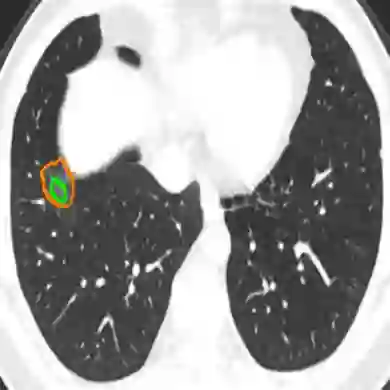

The novel coronavirus disease 2019 (COVID-19) characterized by atypical pneumonia has caused millions of deaths worldwide. Automatically segmenting lesions from chest Computed Tomography (CT) is a promising way to assist doctors in COVID-19 screening, treatment planning, and follow-up monitoring. However, voxel-wise annotations are extremely expert-demanding and scarce, especially when it comes to novel diseases, while an abundance of unlabeled data could be available. To tackle the challenge of limited annotations, in this paper, we propose an uncertainty-guided dual-consistency learning network (UDC-Net) for semi-supervised COVID-19 lesion segmentation from CT images. Specifically, we present a dual-consistency learning scheme that simultaneously imposes image transformation equivalence and feature perturbation invariance to effectively harness the knowledge from unlabeled data. We then quantify both the epistemic uncertainty and the aleatoric uncertainty and employ them together to guide the consistency regularization for more reliable unsupervised learning. Extensive experiments showed that our proposed UDC-Net improves the fully supervised method by 6.3% in Dice and outperforms other competitive semi-supervised approaches by significant margins, demonstrating high potential in real-world clinical practice.